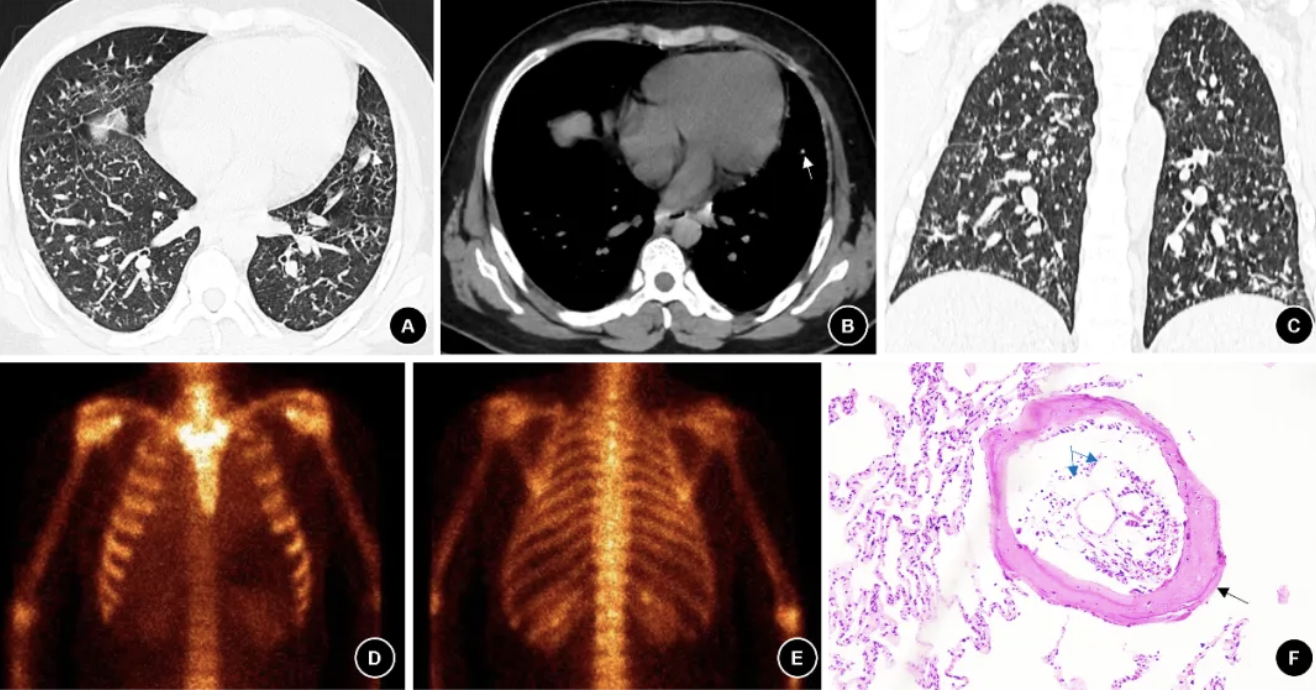

图 4. (例4患者)2021年12月胸部CT,肺窗(A)、纵隔窗(B)、冠状面(C)显示双肺多发高密度小结节伴钙化及分支良好的细线状影,分布较密集(白色箭头);(D)TBLB右下肺组织病理显示气道黏膜(红色箭头)周围可见成熟骨组织(黑色箭头),伴有多量脂肪组织(蓝色箭头)(HE染色 ×200)。

4. 胸部影像学及肺功能表现:4例的胸部CT(图1-4 A-C)主要表现为双肺弥漫性高密度小结节伴钙化、散在分支样细线状影、胸膜轻度增厚。其中2例患者完善99mTc-亚甲基二膦酸盐(Methylene diphosphonate, MDP )全身骨显像(ECT)发现双肺放射性摄取弥漫增高,考虑骨外摄取(图2-3 D-E)。肺功能测试显示3例轻度阻塞性通气功能障碍, 1例限制性通气功能障碍,3例伴弥散功能轻度下降(表2)。

5. 病理学表现:4例诊断均经肺活检病理结果证实。1例在胸腔镜下行外科肺活检(Surgical lung biopsy, SLB),术中发现胸膜表面弥漫性分布粟粒样质硬结节,行楔形切口留取样本;2例行经支气管冷冻肺活检(transbronchial cryobiopsy, TBCB),获得3-4块直径约0.5 cm的肺组织标本;1例行经支气管肺活检(Transbronchial lung biopsy, TBLB)。病理主要表现为镜下观察到肺内成熟骨组织(黑色箭头),其中部分可见脂肪组织(蓝色箭头)(图1D、2F,、3F、4D)。